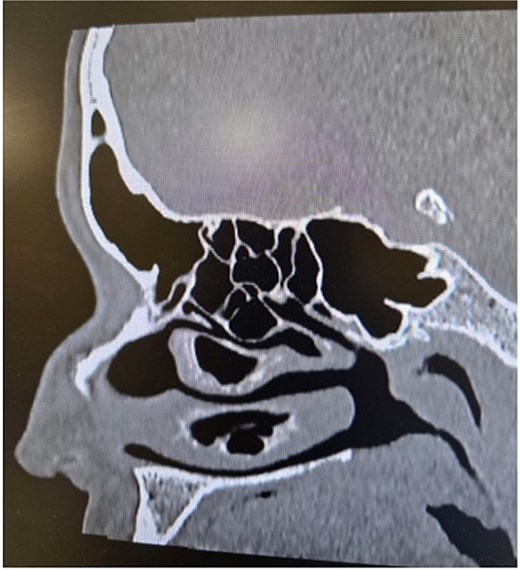

Anterior rhinoscopy and nasal endoscopy demonstrated bilateral hypertrophy of the inferior and middle turbinates, with clear and patent sinus ostia and no evidence of polyps or masses. A coronal CT scan of the paranasal sinuses revealed bilateral ICB and a unilateral CB of the left middle turbinate (Figs 3–5).

Paranasal sinus CT scan in the sagittal plane demonstrating middle concha bullosa and inferior concha bullosa.